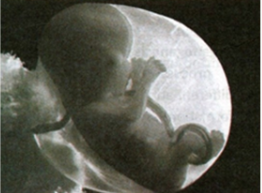

UNIT VI: COORDINATED FUNCTIONS OF THE REPRODUCTIVE, ENDOCRINE, AND NERVOUS